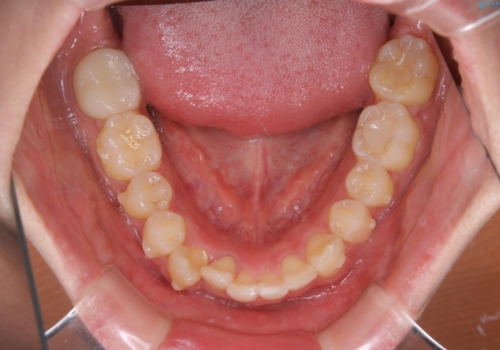

- 口元の突出感は気にならないが、上の前歯の角度と、下の前歯のがたつきが気になるとご相談にいらした方です。なるべく費用や治療期間を抑えて治療したいとのご希望に合わせて治療を計画しました。

この患者様への治療方針として、奥歯から少しずつ歯を移動させる方法と、歯をわずかに削って並べる方法とをご提案しました。短期間での治療を望まれたため、歯をサイズダウンさせて歯を並べました。わずかではあるものの、削った歯は元には戻せないことを十分ご説明し、ご理解ご了承を頂いた上で治療を行いました。